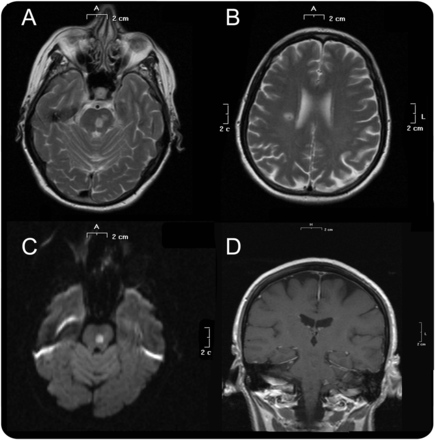

一个67岁的女人面对不稳定和逐渐出现头晕。演讲前两个星期,病人痛苦的水泡疹在左耳后9天内由急性左边缘面部麻痹;拉姆齐亨特综合症的诊断(RHS)和口服valacyclovir开始。几天后启动valacyclovir,她步态不稳,逐渐恶化。她的病史披露控制糖尿病和高血压,和治疗包括二甲双胍,雷米普利,氢氯噻嗪、乙酰水杨酸。神经系统检查,病人无法站立,行走无助的;她有wide-based步态,左侧肢体共济失调为主,双边dysdiadochokinesia。颅神经检查,病人运动神经元低左面部麻痹和疼痛都3左侧三叉神经的分支。深部腱反射、力量和感觉是正常的。头部CT显示左内侧hypodensity脑桥,,因为怀疑中枢神经系统参与的带状疱疹,该患者使用静脉无环鸟苷(每天10毫克/公斤3次)10天。 Brain MRI, performed the second day of therapy, revealed one lesion in the left pons, one in the left midbrain, and one in the right periventricular area. All 3 lesions were hyperintense on T2 and diffusion-weighted imaging sequences and hypointense on apparent diffusion coefficient, consistent with recent ischemic lesions (图)。没有看到其他幕上的或小脑病变。磁共振血管造影(MRA)是正常的。绝对淋巴细胞计数是550 /μL正常(0.95 - -4.40)的反演CD4 +: CD8 + t细胞比例。CSF分析显示40白细胞/μL(主要是单核细胞),40红细胞/μL蛋白质0.46 g / L(正常0.15 - -0.45),和葡萄糖99 mg / dL(正常45 - 80)。CSF带状疱疹PCR是积极和anti-VZV IgG抗体检测CSF。PCR检测其他亲神经的病毒是负的。中风的常见原因包括动脉粥样硬化或解剖被排除在外。2天的静脉无环鸟苷治疗后,病人的症状改善和放电她没有困难站和走单边支持。面部疼痛与卡马西平治疗成功400毫克/天。 At the last follow-up 3 months later, the patient walked without support, retained a mild facial weakness, and denied facial pain after she gradually ceased carbamazepine.

我们描述一个健康、免疫活性的成人患者开发了带状疱疹,发展到小脑性共济失调和三叉神经痛。大脑局部缺血性病变的MRI结果脑干和右半球与小脑参与不一致,在三叉神经功能障碍可能离开脑桥病变的结果。基于1)MRI异常的证据;2)检测带状疱疹DNA和anti-VZV脑脊液免疫球蛋白抗体;3)无环鸟苷治疗后的改善症状;和4)排除另类原因急性小脑性共济失调和中风,病人被诊断患有带状疱疹小脑炎和多病灶的血管病变。因此,我们假设在我们的病人重新激活的带状疱疹膝状神经节引起RHS随后顺行transaxonal传播的病毒通过感官途径小脑和大脑动脉,分别造成小脑炎和三叉神经损伤。虽然平均时间从皮疹出现神经系统症状和体征在带状疱疹血管病变通常是几个月后,他们在一周内可以同时发生或。6tia和中风后并不少见能复活在成人即使没有皮疹,和血管病变是由病毒感染引起的血管。5,- - - - - -,7在我们的病人,查看文档没有任何焦点缩小或大中型脑动脉狭窄,这表明疾病只小动脉在这个病人的影响。急性小脑性共济失调的带状疱疹是极其罕见的成人和带状疱疹后尚未报道。1的确,3成人带状疱疹患者小脑炎没有皮疹的历史文献中均有描述。